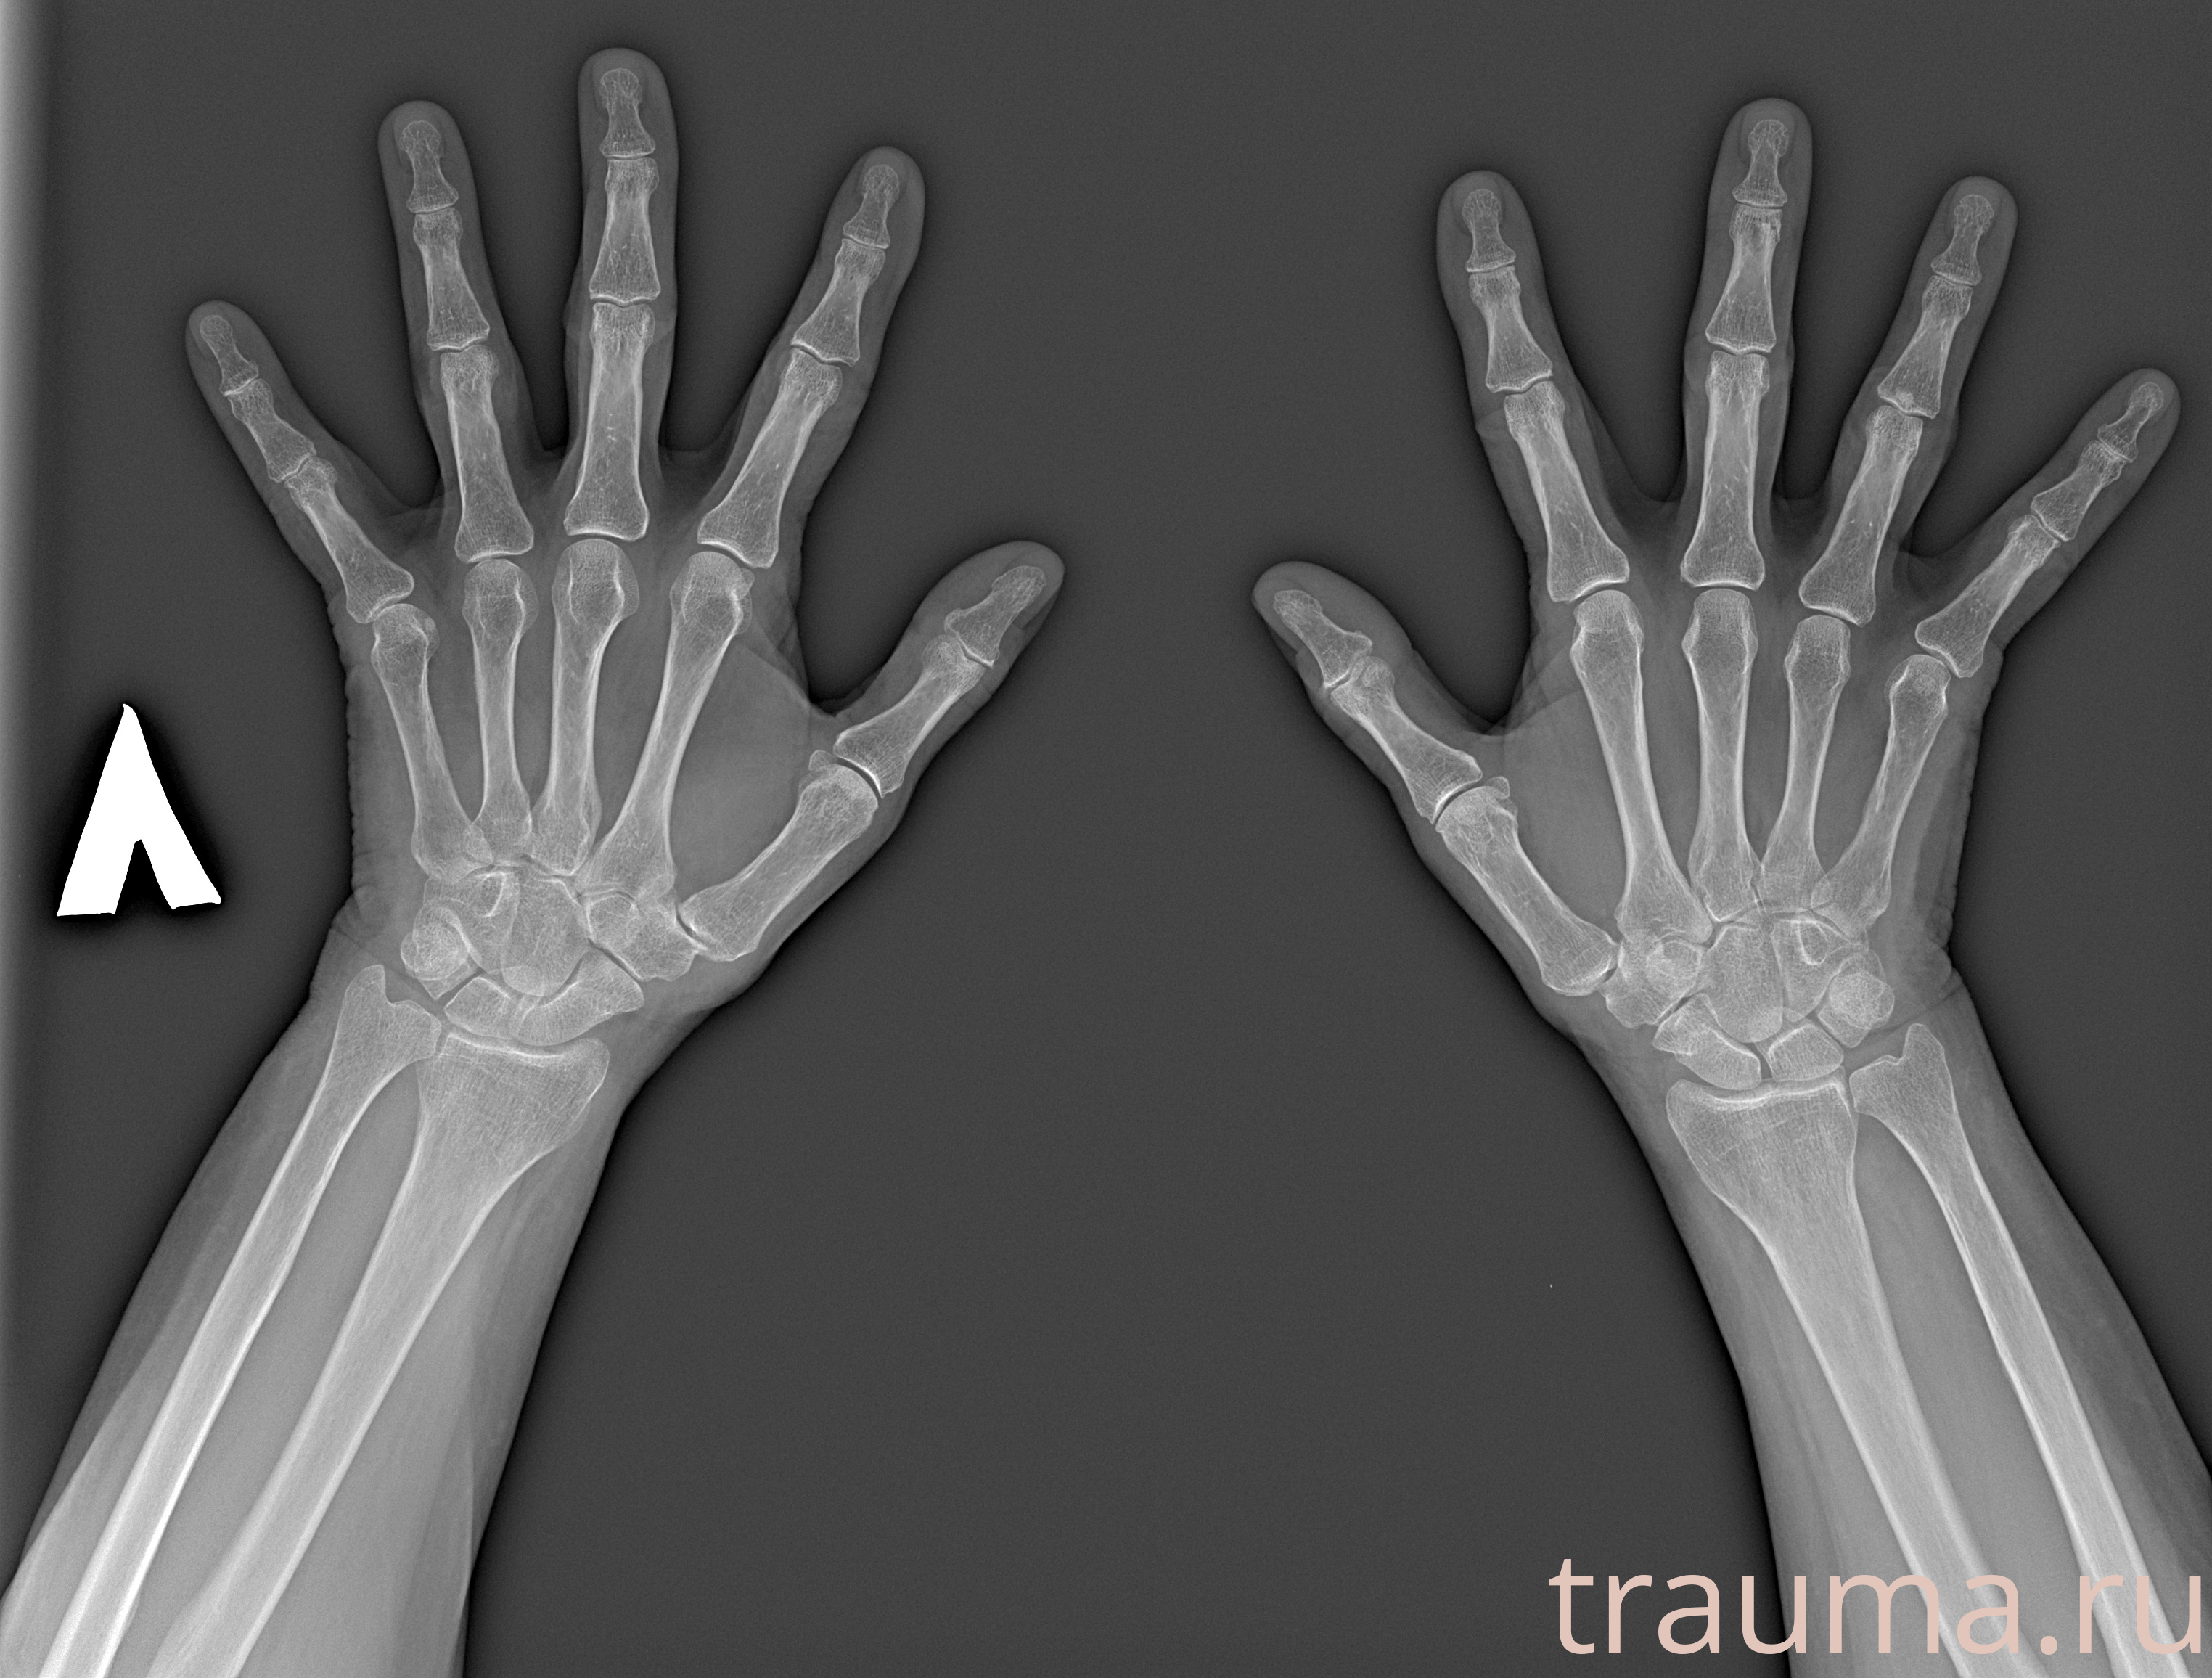

Рентген на дому: по вашему адресу приезжает врач-рентгенолог, травматолог-ортопед с мобильным рентгеновским аппаратом, проводит диагностику травмы или заболевания, делает необходимые рентгенограммы, дает рекомендации по дальнейшему лечению. Получить качественные снимки в домашних условиях возможно благодаря уникальной методике, разработанной МосРентген Центром для института  Склифосовского

при переломе шейки бедра и пневмонии от компании МосРентген Центр - партнера Института имени Склифосовского